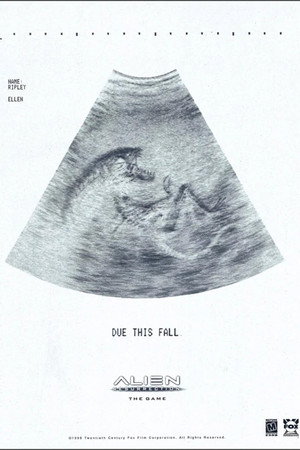

Two hundred years after Lt. Ripley died, a group of scientists clone her, hoping to breed the ultimate weapon. But the new Ripley is full of surprises … as are the new aliens. Ripley must team with a band of smugglers to keep the creatures from reaching Earth.

Original TitleAlien Resurrection

- Science Fiction

- Horror